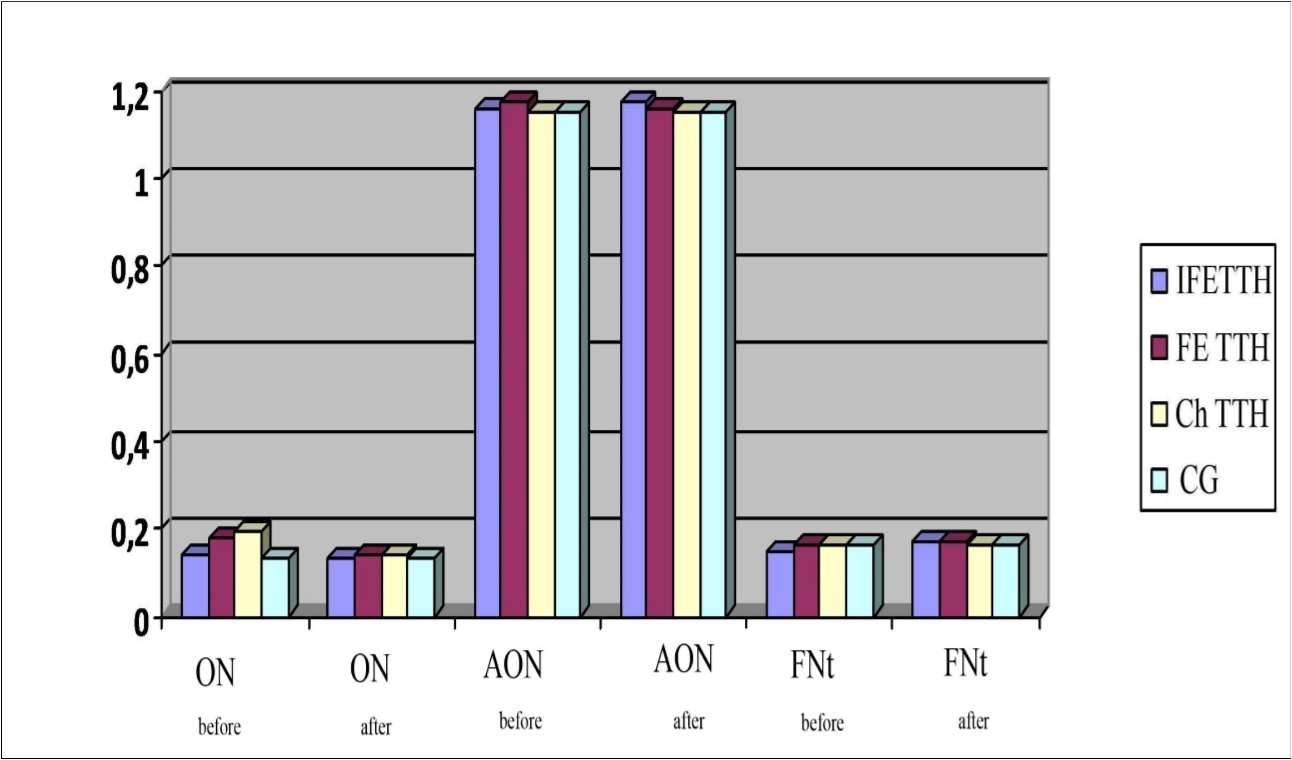

As can be seen from Figure 4 similar results were obtained with the antiorthostatic test (RcAOt) compared with the results of the orthostatic (RcOt) and functional test with nitroglycerin (RcFNt). However, in the study of reactivity to orthostatic, nitroglycerin and antiorthostatic tests there were no significant differences between the parameters of patients with IF TTH, FE TTH, Ch TTH and CG.

Figure 4.Parameters of reactivity coefficient (Rc) to the orthostatic test (Ot), antiorthostatic test (AOt) and functional nitroglycerin test (FNt) in a patients with TTH.

When performing orthostatic and hypercapnic load, a similar (identical) auto-regulating effect of Noofen on vascular reactivity was found. The initially increased RcOt in patients with FETTH decreased from 0.18±0.03 to 0.14±0.2 and from 0.19±0.04 to 0.14±0.03 in patients with ChTTH. No significant changes were observed in initially close to the normative indicators in patients with IFETTH, which once again confirms the selectivity of the influence of Noofen on the mechanisms of vascular autoregulation. A similar picture was characteristic of the initially close to the standard parameters of RcAOt and RcFNt (Figure 11).

Figure 11.Dynamics of RcOt, RcAOt and RcFNt in a patients with TTH during treatment with Noofen